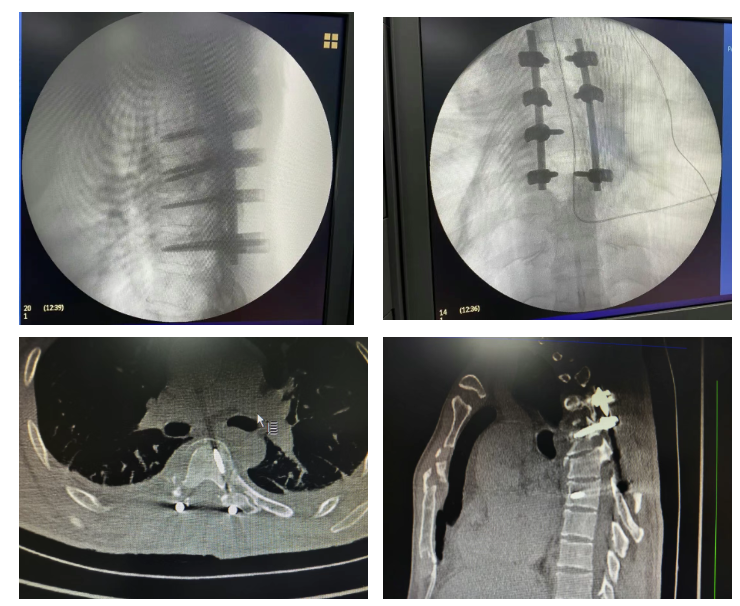

辅助检查进一步明确病情:CT 影像清晰显示患者胸椎多发骨折,胸 5、6 椎体水平椎管受累,骨折块突进椎管内部,直接压迫脊髓,这正是导致患者双下肢活动障碍与小便潴留的核心原因;核磁共振检查同样印证了胸 5、6 椎体对应椎管的受累情况,为后续治疗方案制定提供了精准依据。

手术中,医护团队默契配合,精准实施胸椎骨折切开复位内固定术 + 椎管减压术(T4-7),手术最终顺利完成。术后即时评估显示,患者下肢麻木、疼痛症状较术前有明显改善,下肢肌力也出现初步恢复迹象,为后续康复奠定了良好开端。